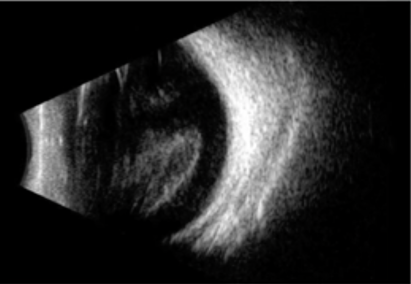

Loss of red reflex is seen in 20% of eyes with Terson syndrome[2]. B-scan may be used to confirm vitreous hemorrhage when no view to the fundus is present (Fig. 4). Orbital CT scan may detect Terson syndrome in two-thirds of cases, showing retinal crescentic hyperdensities and retinal nodularity [43][28].